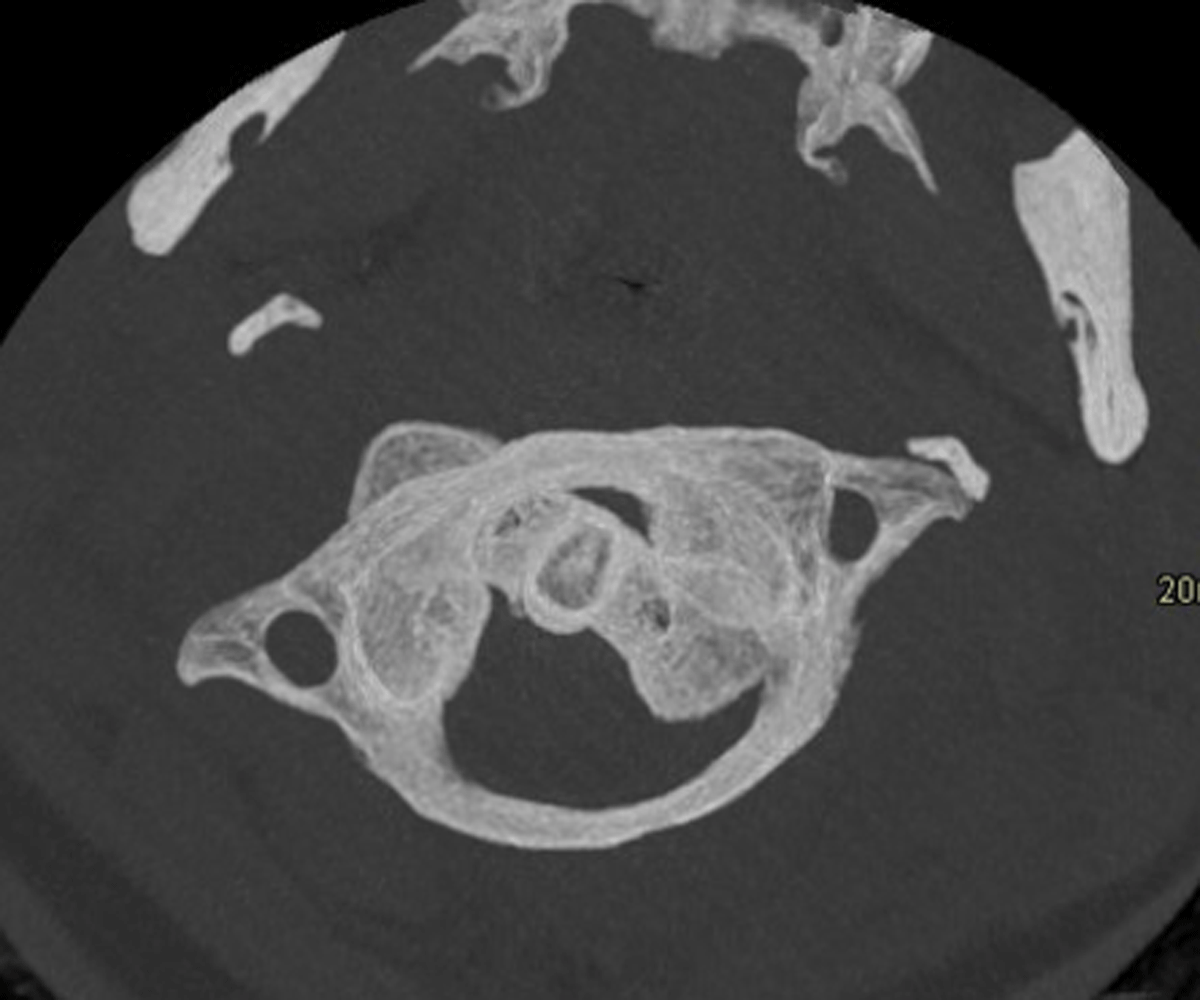

A 19-year-old female presented to the emergency department for neck pain and stiffness of two weeks duration following a sharp neck movement. Axial 15-mm-thick maximum intensity projection of cervical spine CT suggested the diagnosis of Fielding type I AARF on the basis of rotation of C1 on C2 (Figure 1). The patient was discharged. Persistent neck pain led to re-admission. Magnetic resonance imaging (MRI) evidenced exclusive C1–C2 rotation. A ‘dynamic’ CT with maximal left-sided head rotation confirmed the fixed character of the C1–C2 complex as they rotated as a unit (Figure 2).

Figure 2

Atlas and axis rotate as one unit on CT with maximal contralateral head rotation.

Dynamic CT with the head in the neutral position followed by maximal contralateral rotation of the head confirms the diagnosis of type I; the deformity remains fixed, differentiating pathology from voluntary head rotation or other causes of torticollis.